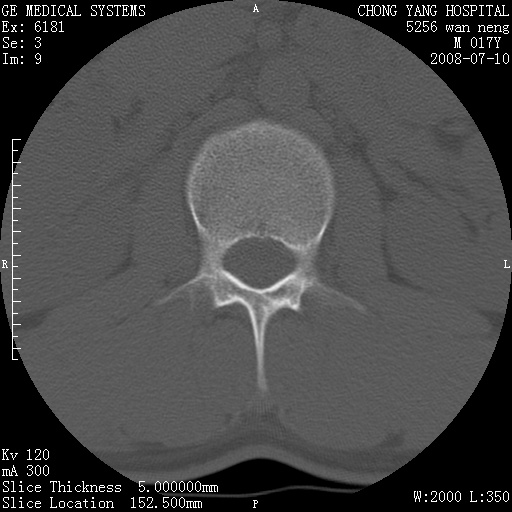

腰3、4椎弓崩裂

腰3、4椎弓不连

支持:腰3、4椎弓峡部崩裂。

腰3、4椎弓峡部不连

支持:腰3、4椎弓峡部崩解。

腰3、4,如受过外伤则为陈旧骨折,否则为骨质不连

图片漂亮,目前也只能看到腰3、4骨质不连

腰3、4椎弓峡部裂。

腰3、4椎弓峡部裂。支持

重建图像见多个椎弓峡部不连(不足为据),平扫未见异常。

支持腰3、4椎弓峡部崩裂。